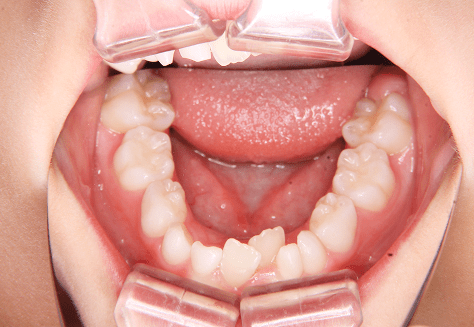

M.M

治療前

治療後

主訴

嚙み合わせが悪い。八重歯が気になる。

診断

叢生・反対咬合

年齢/性別

10代/女性

抜歯部位

非抜歯

使用装置

インビザラインファースト→インビザラインフェーズⅡ(部分的にワイヤーにて処置)

保定装置

上下ビベラリテーナー

料金

初回資料採得・・・・・・・30,000円

診断料・・・・・・・・・・0円

動的治療終了時資料採得・・5,500円 -

基本料金

円ファースト時:450,000円

フェーズⅡ時:240,000円 -

診察料金

ファースト時:0円×16回

フェーズⅡ時:5,500円×9回

ワイヤー併用時:8,800円×2回 -

治療期間

2年7カ月